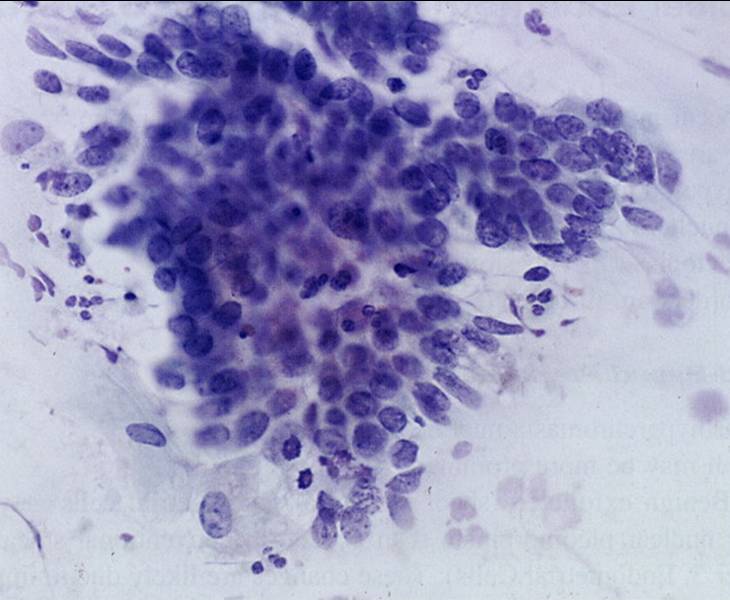

TBS-51.HSIL CIN3

TBS-52.HSIL CIN3

TBS-53.HSIL CIN3

TBS-54.HSIL CIN3

TBS-55.ASC-H:不能排除高度鳞状上皮病变的不典型鳞状细胞

TBS-55.HSIL

TBS-56.HSIL

TBS-57.HSIL

TBS-58.HSIL

TBS-59.HSIL